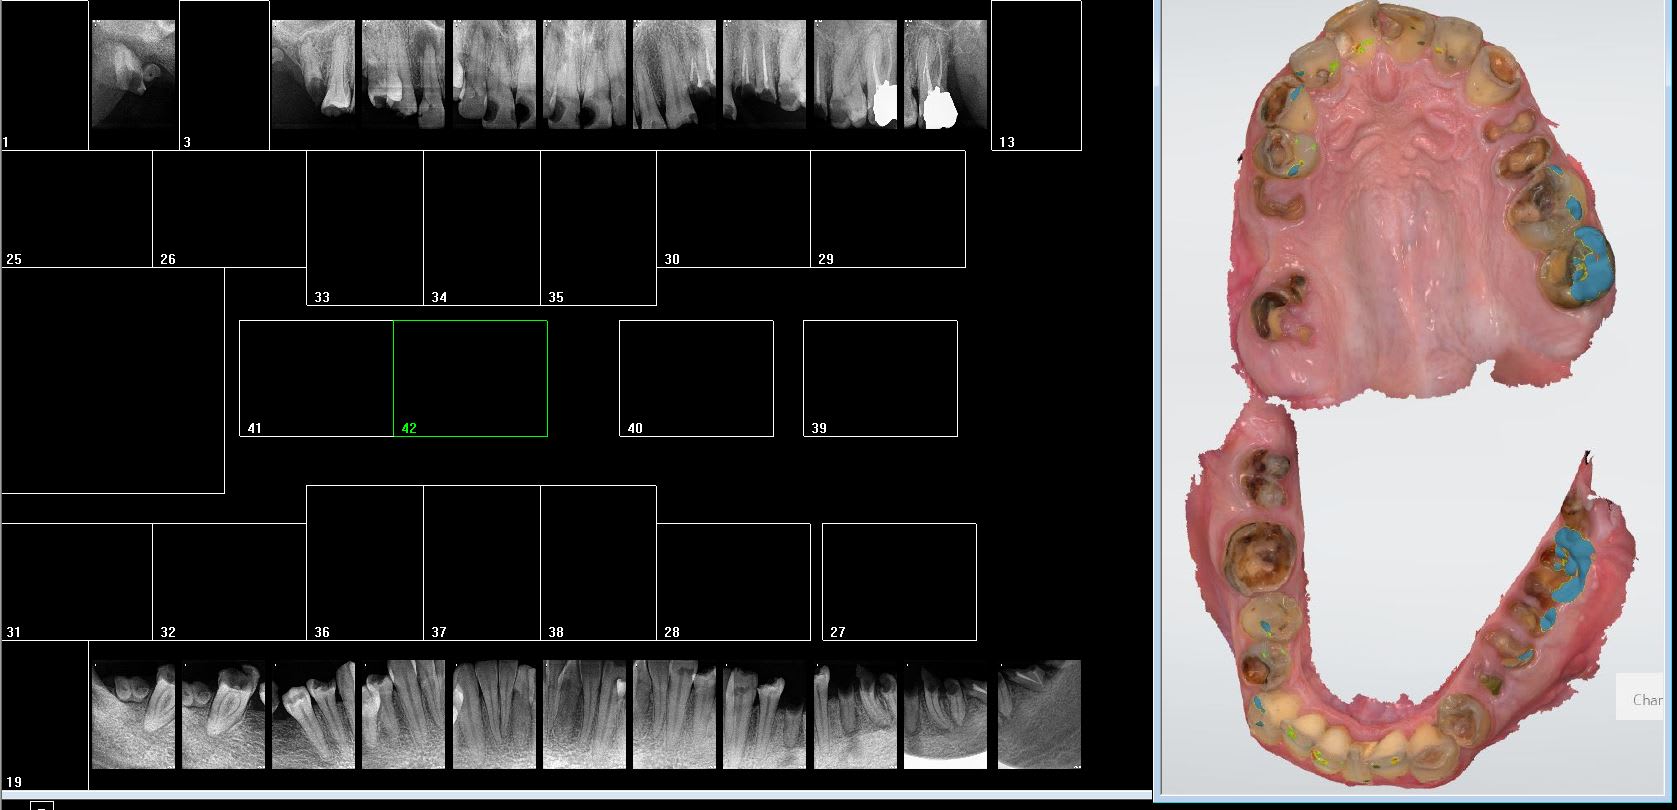

Déjà tu te fais plus chier à choisir des porte empreintes. Ensuite tu changes de labo quand tu veux pour n'importe quel travail. Et puis tu fais tes empreintes d'étude en meme temps que ton status radio pour réfléchir à tête reposée pour tes plans de tt. Chaque empreinte prend entre 30 secondes et une minute autant te dire que tu en fais pour un oui ou pour un non.